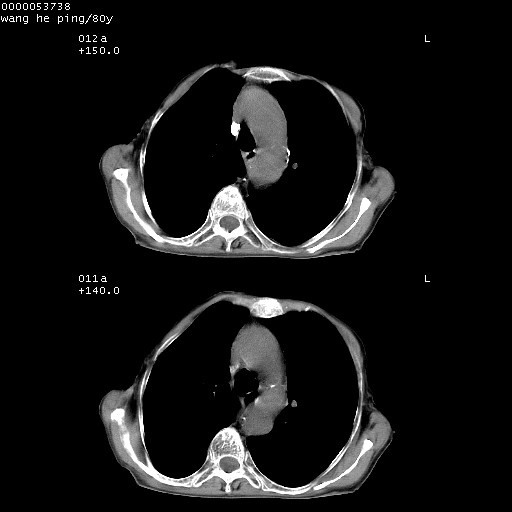

以下是引用黑白光影在2008-8-28 22:33:00的发言:[br]右肺中央型肺癌伴阻塞性肺炎,肺癌肺转移。

以下是引用lshx在2008-8-28 22:06:00的发言:[br]1.右肺中心型肺癌伴阻塞性肺炎,不除外双 肺早期转移。[br]2.心包积液。

以下是引用随光逐影在2008-8-29 7:40:00的发言:[br]1)右肺中心型肺癌伴阻塞性肺炎,肺内转移。2)心包积液(少量)。

以下是引用wqs571018在2008-8-28 21:56:00的发言:[br]右肺中心型肺癌伴阻塞性肺炎可能。

以下是引用liuyue在2008-8-28 22:46:00的发言:[br]1.右肺中心型肺癌伴阻塞性肺炎。[br]2.心包积液(少量)。